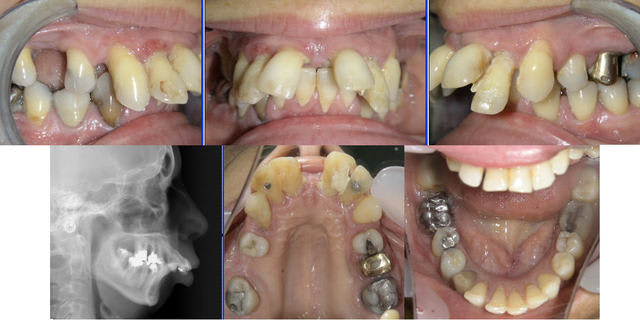

Voici un petit cas… Elle (c’est une femme) a 53 ans.

J’ai l’intention de réaliser un traitement orthodontique pour remettre un peu d’ordre et rentrer ses incisives dans l’os.

Comme la 21 nécessite à l’évidence un traitement radiculaire, doit-on en profiter pour traiter également les trois autres incisives supérieures ?

Quoi qu'il en soit, voici les derniers clichés.

Il ont été pris 1 an après la fin du traitement. Attelles de Genon et gouttière de protection supérieure nocturne à porter "à vie".

C'est le statu quo.

Ma question demeure : 21 est moins résorbée que les autres, est-ce dû au traitement radiculaire où à la "pêche" apicale qui a offert une moindre résistance à l'ingression ?

J'aurais aimé que nos experts répondent avant de voir qu'il y a effectivement une différence, mais puisque tu m'as demandé la pano, je m'exécute..